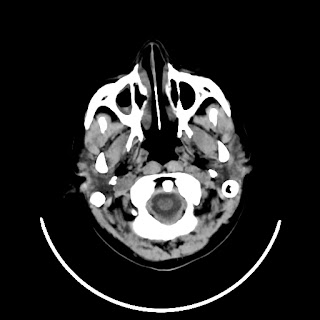

A 33 years old woman with protruding eyeballs & hyperthyroidism since 2 years